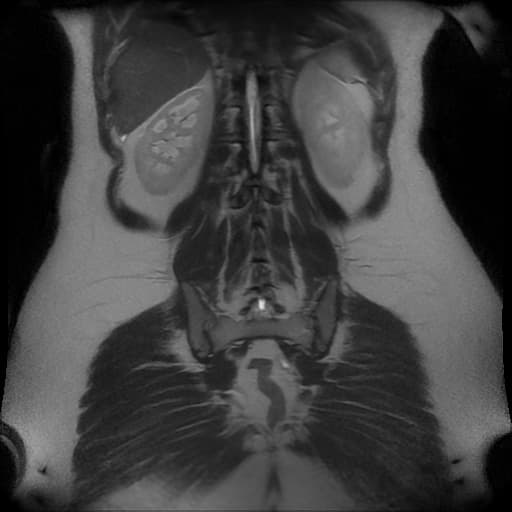

- Túi mật chứa nhiều viên sỏi, được hiển thị rõ trên các chuỗi xung MRI khác nhau.

- Các sỏi được xác định rõ nhất trên hình ảnh trọng T2 và MRCP do chúng hiện lên như các vùng giảm tín hiệu (hypointense) trong lòng túi mật.

- Không thấy hình ảnh dãn ống mật chủ (dilated common bile duct).

- Gan và các đường mật trong gan không có hình ảnh bất thường.

- Tụy, thận và các cấu trúc ổ bụng khác không có tổn thương đáng kể.

Sỏi túi mật, hay còn gọi là cholelithiasis, thường được phát hiện tình cờ hoặc ở bệnh nhân có các triệu chứng như đau quặn mật hoặc rối loạn tiêu hóa. MRCP là phương tiện hình ảnh không xâm lấn, hiệu quả cao, sử dụng các chuỗi xung trọng T2 để hiển thị dịch đứng yên trong hệ thống đường mật. Các viên sỏi hiện lên như những khuyết thiếu tín hiệu giảm đậm độ rõ ràng trong lòng túi mật hoặc ống mật. Khác với siêu âm, MRCP cung cấp hình ảnh rõ nét toàn bộ hệ thống đường mật, kể cả đoạn cuối ống mật chủ, mà không bị ảnh hưởng bởi hơi ruột hay thể trạng bệnh nhân. MRCP không cần thuốc cản quang hay tia bức xạ, do đó rất phù hợp để đánh giá các bệnh lý đường mật nghi ngờ khi siêu âm không kết luận được. Tuy nhiên, MRCP không đánh giá được chức năng túi mật hay tình trạng viêm thành túi mật, nên việc kết hợp với lâm sàng là cần thiết.